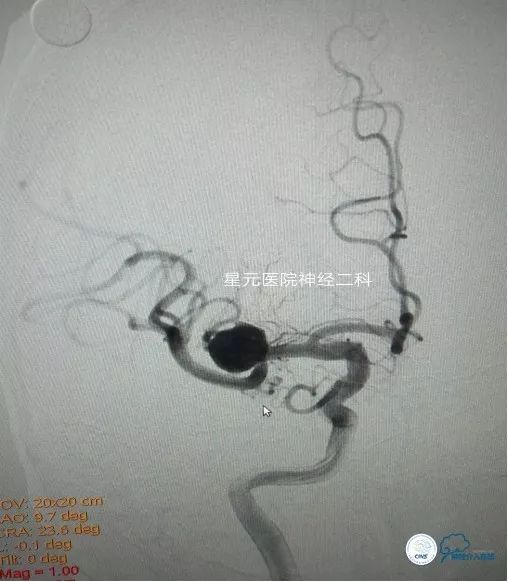

患者,男,69岁,以“左侧肢体力弱、麻木35天”主诉入院。头颅CTA:双侧大脑中动脉分叉前后段交界处动脉瘤。入院前曾因“动脉瘤破裂出血”在当地医院住院治疗21天。

DSA回报:右侧大脑中动脉分叉处可见一14mm×11mm椭圆形动脉瘤,载瘤动脉为大脑中动脉M2段主干,其眶额支直接发自瘤体底部。左侧大脑中动脉分叉处可见一5mm×4mm球形动脉瘤。